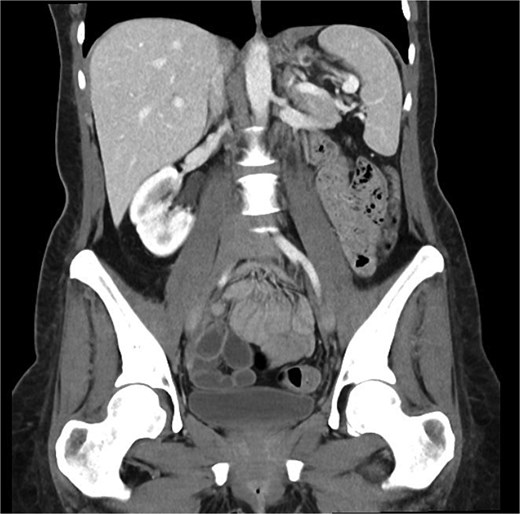

On follow up six months post-procedure, a CT scan demonstrated no ongoing collection with mild thickening of the left hemidiaphragm (Fig. 2), and a barium swallow showed normal passage of contrast. While radiographically mostly reassuring, clinically the patient reported persistent dysphagia and post-prandial vomiting resulting in significantly reduced oral intake and weight loss. Notably, she also reported left shoulder pain associated with eating. A gastroscopy was performed wherein mediastinal migration of the proximal staple line was diagnosed. The previous defect located at the proximal staple line of the stomach remanent was interrogated but the repair remained intact.

Coronal portal venous phase CT scan of the abdomen and pelvis demonstrating the thickening of the left hemidiaphragm but nil evidence of ongoing leak.